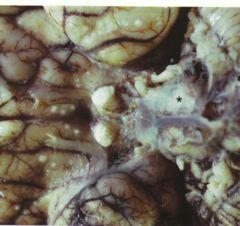

椎管内结核肉芽肿又叫椎管内结核瘤,椎管内结核瘤是继发于身体其他部位的结核病变,结核菌绝大多数是由身体其他部位的结核病灶经血行播散到椎管内,

结核性脑膜炎的病变也可以直接播散侵犯脊髓。椎管内结核肉芽肿是由原发病灶的结核病转移病转移,或结核菌经血行或淋巴侵入脊柱的结果,结果是引起脊柱破坏和硬脊膜外冷脓肿结核性肉芽肿。